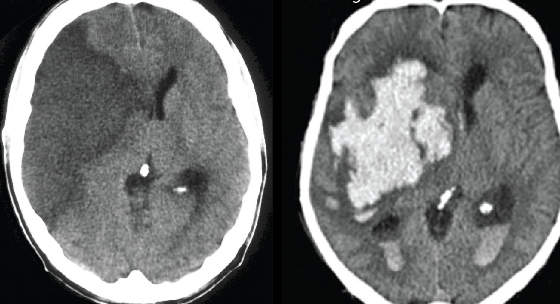

Identify

Area of hyperdensity (white)→ Hemorrhagic

Area of hypodense (dark) → Ischemic